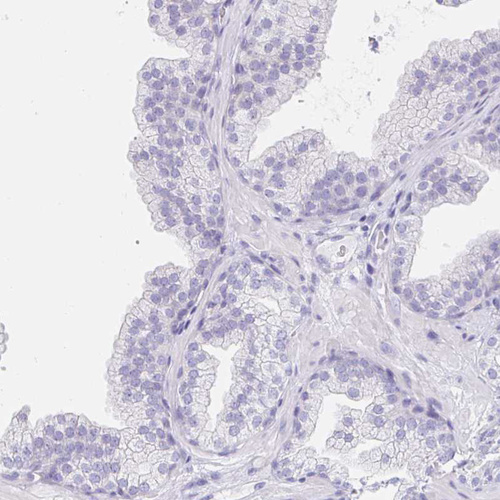

Immunohistochemistry analysis in human testis and prostate tissues using HPA015504 antibody. Corresponding EQTN RNA-seq data are presented for the same tissues.